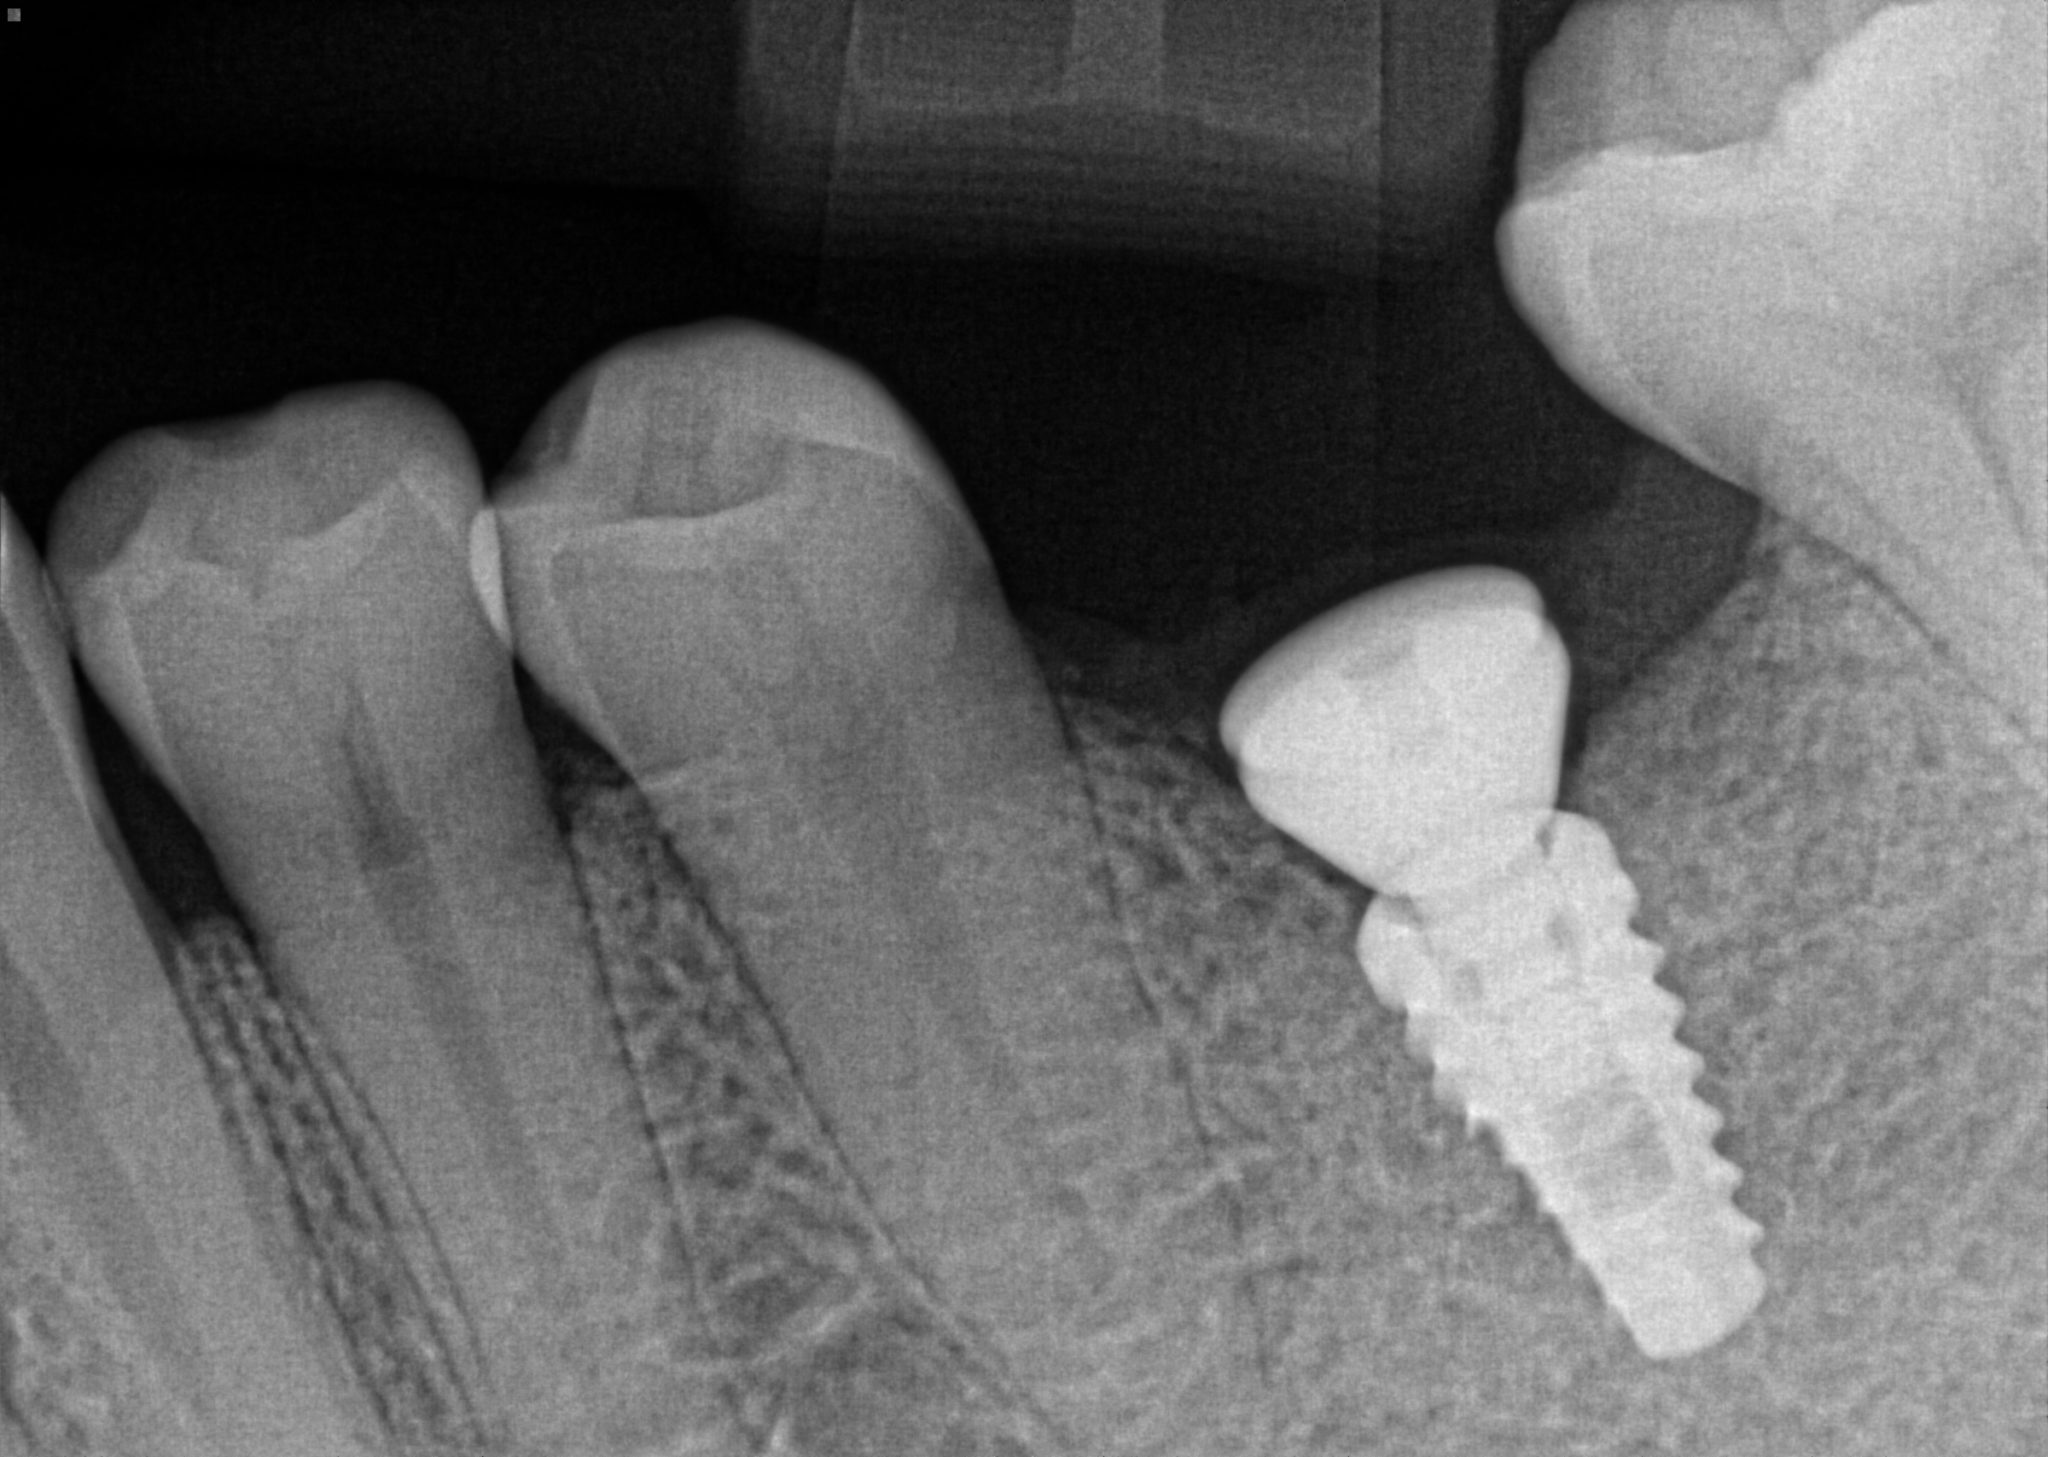

26 Radiograph of an abutment on an externally hexed implant that is not Implant Abutment Not Seated The number one reason for prosthetic misfit is usually due to the clinician taking inaccurate impressions that can lead to. I use an implant system where i have to insert the abutment and then turn counterclockwise for the abutment to fully. As we know, abutments can seat in multiple positions depending on the implant system being used. If you did. Implant Abutment Not Seated.

Importance of taking a radiograph to verify accurate interface of the Implant Abutment Not Seated If you did an all on x / all on 4 procedure and your multi unit abutment didn’t seat all the way,. As we know, abutments can seat in multiple positions depending on the implant system being used. How the implant abutment screw joint works. As operators controlling the screw joint, dentists can reduce the risk of. I placed a. Implant Abutment Not Seated.